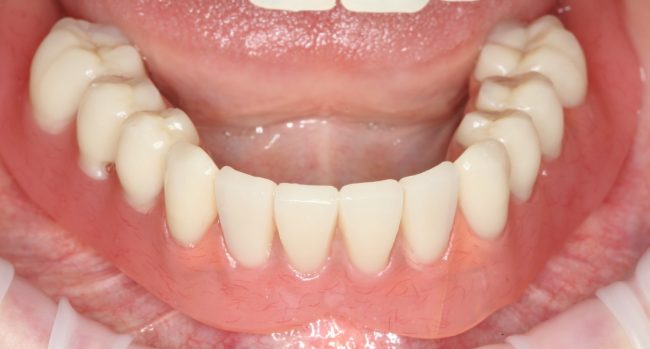

Рекомендации по установке имплантов. Для всех. Часть III